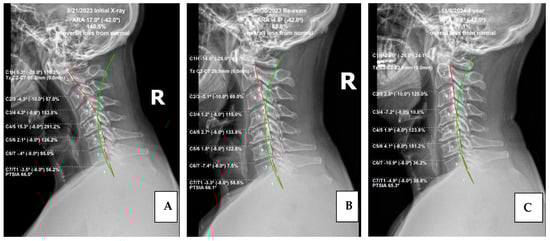

Post-MVC Cervical Kyphosis Deformity Reduction Using Chiropractic BioPhysics Protocols: 1-Year Follow-Up Case Report

by Nicholas J. Smith, Thomas J. Woodham and Miles O. Fortner

Background/Objectives: This case represents the successful treatment of cervical spine injury from high-speed rear-impact motor vehicle collision and abnormal cervical kyphosis with left arm radiculopathy, utilizing conservative spine care rehabilitation methods. This patient was treated with a multimodal treatment approach integrating a cervical [...] Read more.

Background/Objectives: This case represents the successful treatment of cervical spine injury from high-speed rear-impact motor vehicle collision and abnormal cervical kyphosis with left arm radiculopathy, utilizing conservative spine care rehabilitation methods. This patient was treated with a multimodal treatment approach integrating a cervical spine extension traction protocol. Subject and Methods: A 50-year-old male with a history of motor vehicle collision presented with left arm radiculopathy, as well as cervical and upper thoracic spine pain. Notably the cervical spine presented with kyphotic deformity. The patient presented, after a being struck during a rear-end motor vehicle collision, with neck, upper back, and left arm radiculopathy. Prescription medication and traditional chiropractic care proved ineffective for substantive symptom and quality-of-life improvement. Treatment frequency was three times per week for eight weeks using the Chiropractic Biophysics® protocol of mirror image (MI®) postural exercise, spinal adjustment, and cervical spinal traction. On completion of in-office care, the patient was treated monthly, performed home care at least three times per week, and was re-examined at one year. Results: Final examination after eight weeks of care showed significant improvement in cervical lordosis (21.8 degrees), resulting in reduced cervical kyphosis. The patient completed outcome indices before, during, and 12 months after cessation of active care, all indicating improvement. Conclusions: This case report demonstrates both subjective and objective improvement in cervical spine kyphosis and attendant symptoms. The successful treatment of chronic pain, peripheral weakness, and radiculopathy with long-term follow-up using CBP care is documented as well. The treatment was designed to improve sagittal balance and reduce radiographic abnormalities evincing spinal misalignment. Administration of subjective, objective, and health-related quality-of-life outcome indices during, following, and 12 months post-treatment are suggestive of long-term efficacy of Chiropractic BioPhysics® (CBP) treatment methods. Larger studies are needed to substantiate this given the limitations of a case report. Full article

Show Figures

Figure 1